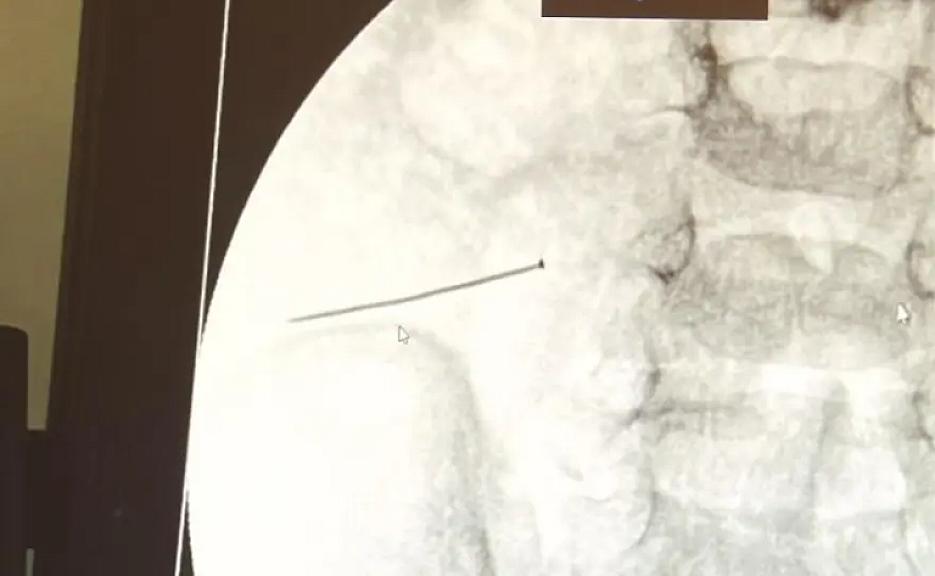

İstanbulda iki yaşlı körpə sancağı udub və iynə onun bağırsağını deşib.

E-saglam.az xəbər verir ki, uşağın qarın ağrısı və davamlı ağlaması ailəni narahat edib. Nənəsi tərəfindən xəstəxanaya aparılan uşağa edilən rentgen müayinəsində təxminən 3 santimetr uzunluğunda sancaq aşkarlanıb.

İlhan Varank Sancaktepe Təlim və Araşdırma Xəstəxanasında keçirilən əməliyyat zamanı sancaq uğurla çıxarılıb. Tibb üzrə dosent, şəhid professor Dr. Sefa Sağ bildirib ki, bu vəziyyət çox təhlükəli idi və vaxtında müdaxilə edilməsəydi ağır nəticələr doğura bilərdi.